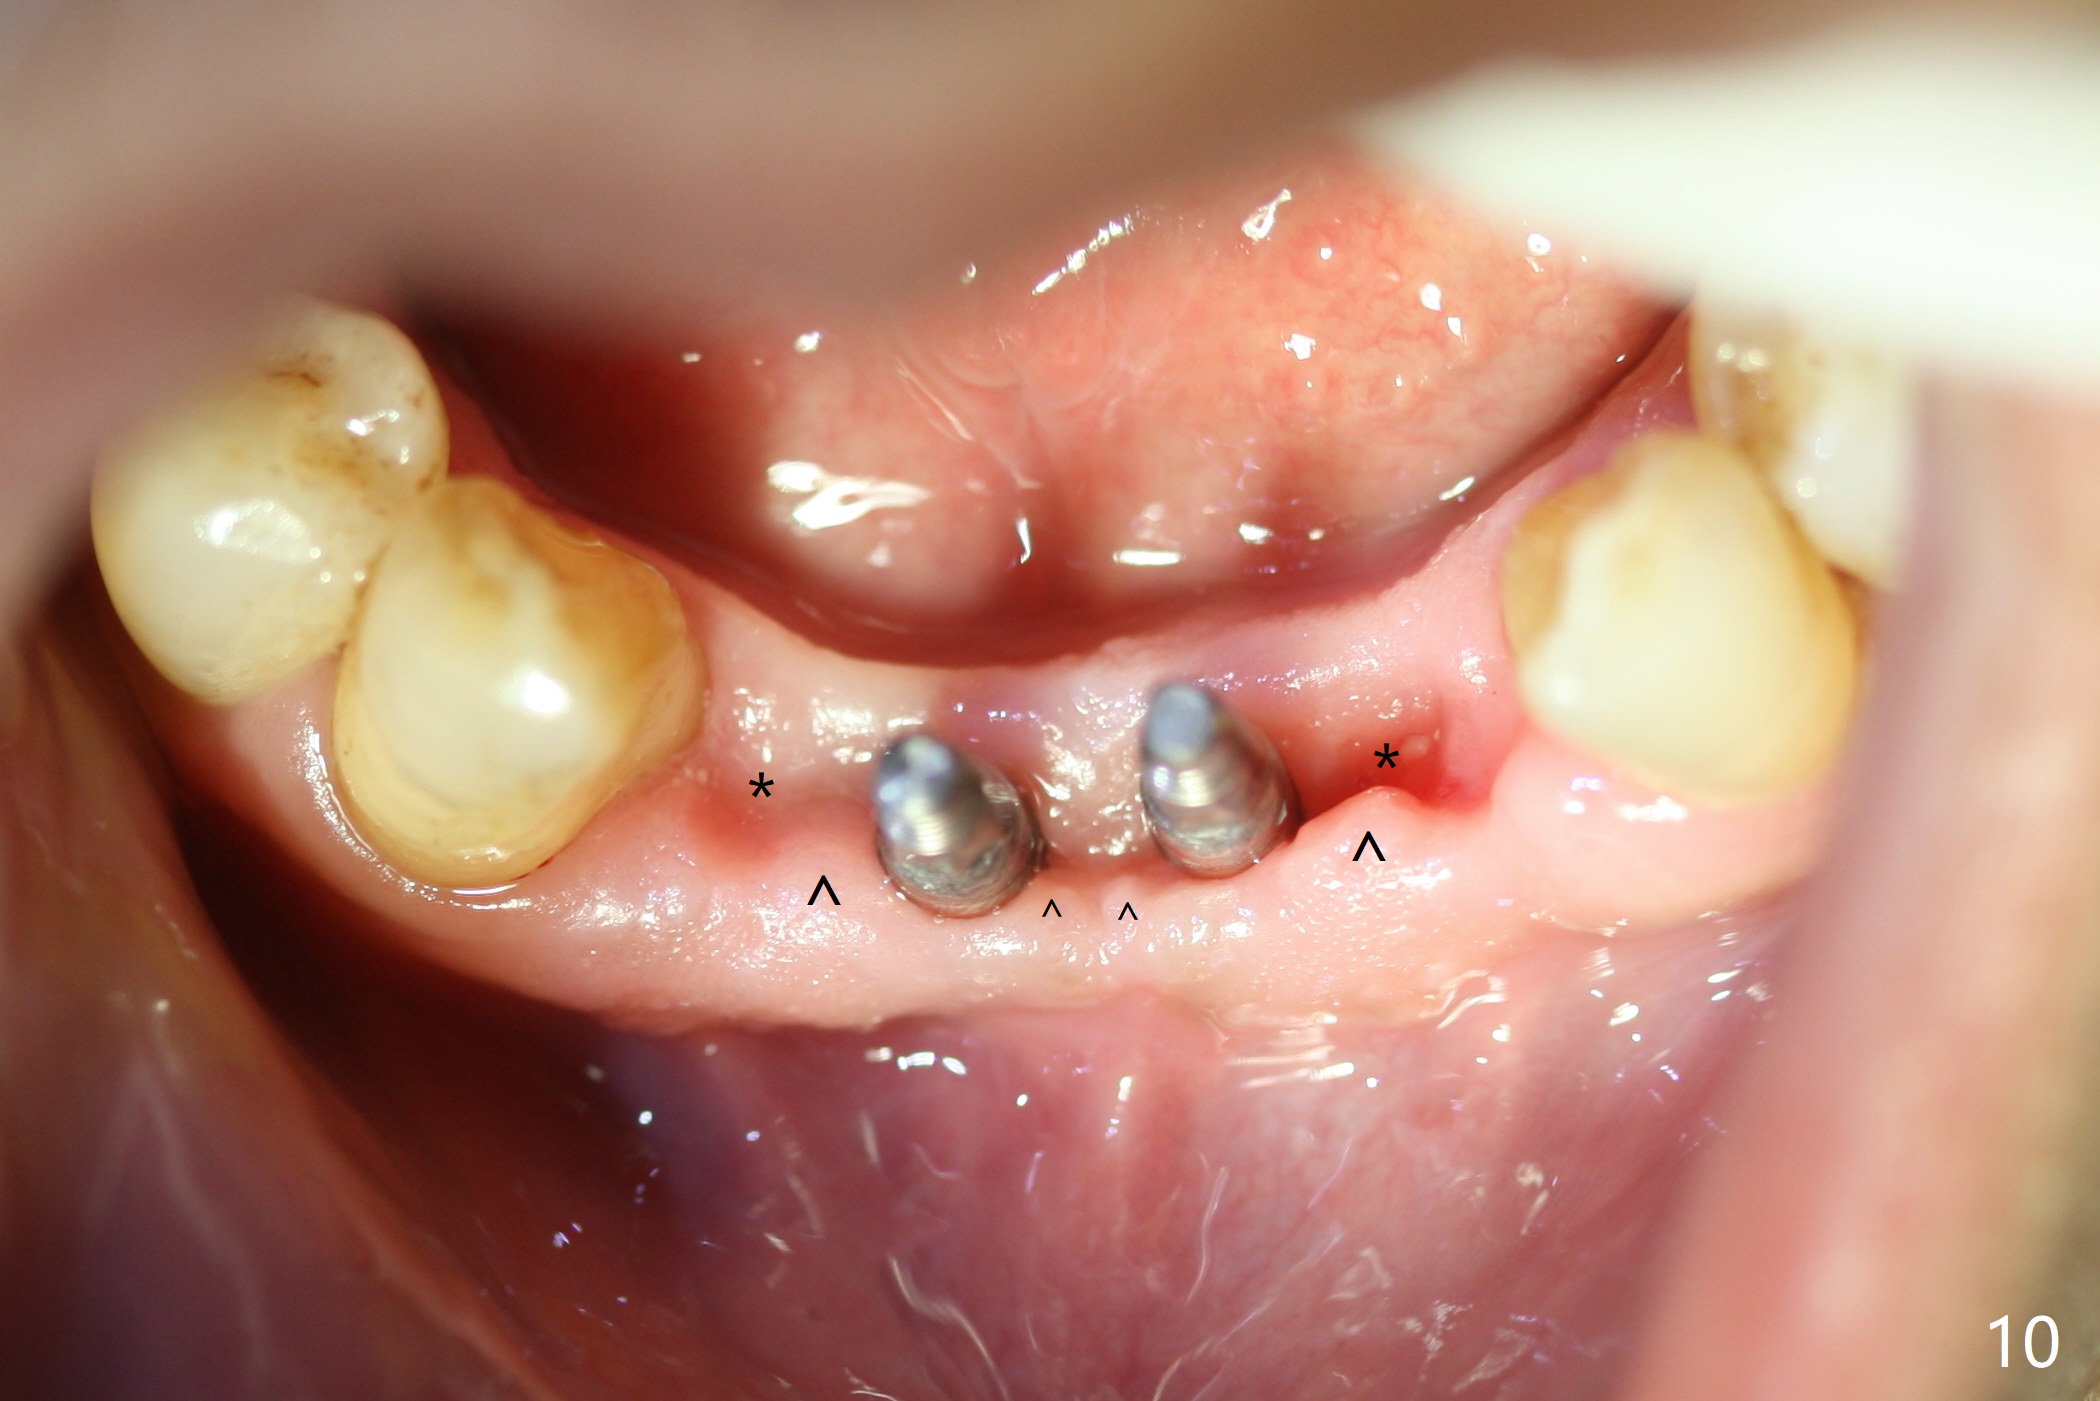

When the patient (smoker) returns for treatment, the apical abscess associated with #25 and 26 reduces with oral Amoxicillin. He agrees with 4 incisor extraction because of 2 apical fistulae (Fig.1 >). Osteotomy starts at the central incisor sockets due to mesial root exposure of the canines (Fig.2 arrowheads) and buccal alveolar bone fracture between #23 and 24 (Fig.7). Two of 3x14(4) mm 1-piece implants are placed with ~ 2 mm buccal gap (Fig.3). After Vanilla graft is placed in the bony defects (Fig.5 *) and Osteogen plug, sutures are placed (Fig.4). The implants are then placed deep to decrease thread exposure (Fig.6). Periodontal dressing is applied instead of provisional. Alveolar bone fracture between #23 and #24 accounts for why an implant is less suitably placed at #24 (Fig.7). Three months postop, composite is added to the pontic areas of the provisional (Fig.8 *). When the provisional is seated, the convex pontics press the used-to-be-flat gingiva (Fig.9 arrows). Thus the concave gingiva forms (Fig.10 *) with corresponding papillae (^). In fact the photos of Fig.8-10 is taken ~3 weeks later. Most of the grafted bone remains in place 3.5 months postop (Fig.11). A piece of floss with 2 knots in one end is placed between the middle units of the final bridge before cementation (Fig.12 (4 months 10 days postop)). In fact removal of residual cement is not so simple. It is tedious (Fig.13,14). An asymptomatic buccal fenetration with implant thread exposure is found 2 months post cementation and persists for another month in spite of advice to reduce smoking (1/2 ppd) and use of water pik (Fig.15). The area will be debrided, followed by bone graft and PRF in a month.